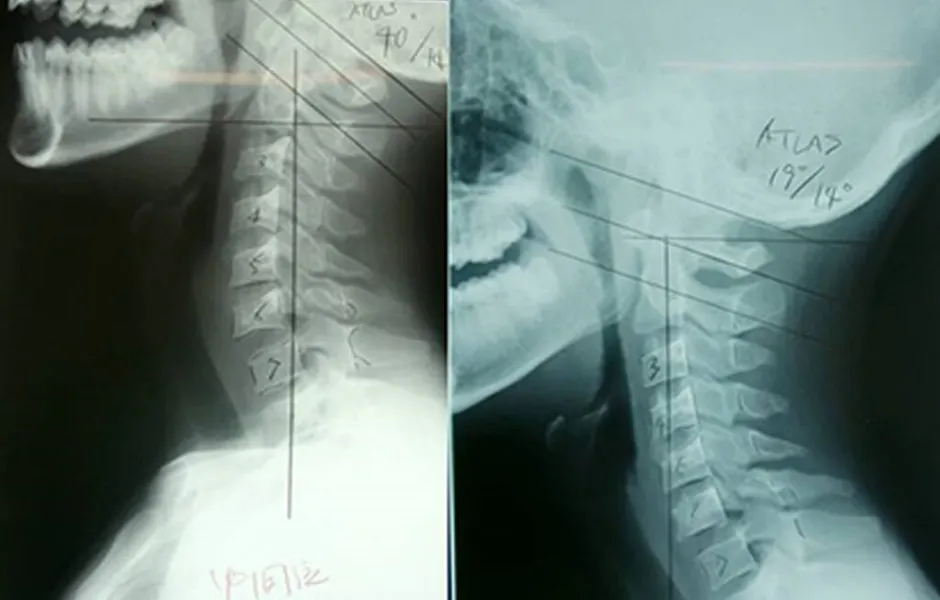

- アトラスオーソゴナルカイロプラクティックは、第一頚椎(アトラス)1 箇所のみを微調整することにより、全身の骨組みを瞬時に矯正することのできる近未来的な施術法です。

「第一頚椎(アトラス)」へのアプローチであらゆる症状を解決

第一頚椎(アトラス)の僅かなズレが様々な症状の原因となることは知られていません。

第一頚椎(アトラス)1ヶ所のアプローチで、骨格の歪みに起因する症状や自律神経系及び神経の伝導に関わ症状などあらゆる症状を解決します。